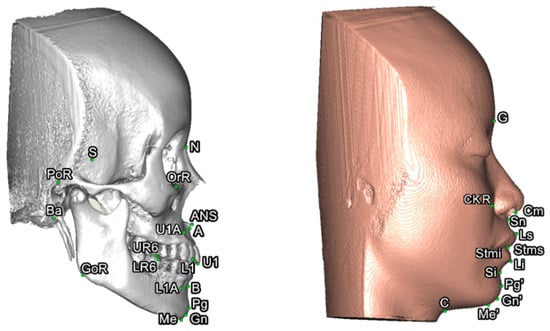

To set a normative database of 3D Burstone cephalometric measurements for Taiwanese Chinese, a total of 27 linear and nine angular measurements were generated using Simplant software. For this, all craniofacial bone and soft-tissue anatomical landmarks and reference planes (22, 14, and 8 parameters, respectively) were standardized based on previous descriptions (Table 1 and Table 2, Figure 2 and Figure 3) [11,12,33,34,35]. Two Burstone analysis-related anatomical landmarks (i.e., PtM and Ar) [11,12] were adapted; the anterior base length (S-N) replaced the cranial base length (Ar-PtM-N) and the Co-Go replaced Ar-Go for ramus length measurement. Due to the relevance of cheek prominence for overall aesthetic balance in Asians [25,36,37,38], a further parameter—that is, cheek mass (CK) (Figure 4)—was added to the Burstone soft-tissue analysis.

Figure 2. Three-dimensional skeletofacial model displaying the reference planes used for cephalometric analysis: (1) X, horizontal plane; (2) Y, midsagittal plane; (3) Z, vertical plane; (a) N plane; (b) FH plane; (c) palatal plane; (d) occlusal plane; and (e) mandibular plane.

Figure 3. Three-dimensional skeletofacial model displaying the bone and soft-tissue landmarks adopted for cephalometric analysis. For definitions, please, refer to Table 1.

Figure 4. Location of cheek mass (CK) for cheek prominence measurement. To represent the most projected point on the cheek contour, the CK point was located on the most convex point on the mid-pupillary plane (vertical line) below the infraorbital area. The horizontal distance between CK and mid-pupillary vertical line was measured. For definitions, please, refer to Table 1 and Table 2.